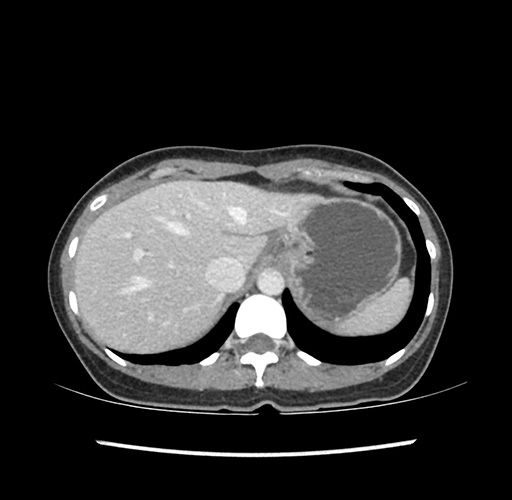

Imaging Analysis

Look through the patient's CT scan to identify any areas of concern for the necessary procedure.

Based on your CT findings, which issue(s) would give reason for "planned slowing down moment(s)" in this case?